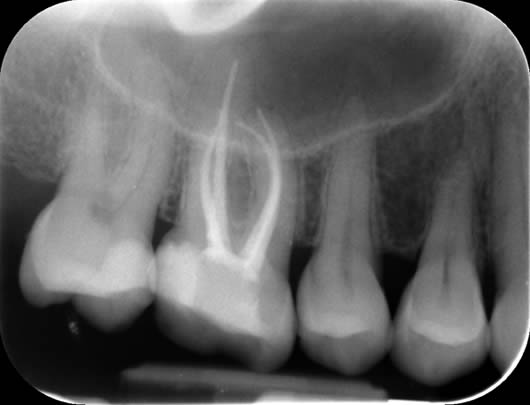

Case 1: Root canal treatment – long roots.

This patient presented with a history of a dull pain and swelling from his upper left second molar (UL7). The tooth had a crown and was tender when tapped. A radiograph (X-ray photograph) showed that there was a large shadow around the roots. This shadow indicates bone loss caused by infection within the root canals. The diagnosis for this tooth was ‘Chronic apical periodontitis’; and the treatment options were either extraction or root canal treatment. After discussion with the patient, we decided to proceed with root canal treatment. As the crown was in good condition, we decided to keep it in place and access through the top of it. This way, a new crown would not be needed after our treatment. In this tooth, all the canals were found; they were long but after careful progress we were able to negotiate to the ends of the roots. This is important as it means we can take our disinfectant solutions to the full length of the canals, enhancing our cleaning potential. The canals were prepared (enlarged to improve penetration of the cleaning solutions), cleaned and filled. A radiograph taken after one year shows good healing as the ‘shadow’ has gone due to regeneration of bone.

Before treatment UL7 - note the ‘shadowing’ around the roots.

Following root canal treatment - the ‘white lines’ are the root fillings within the root canals.

One year review – note the healing of the previous ‘shadow’.